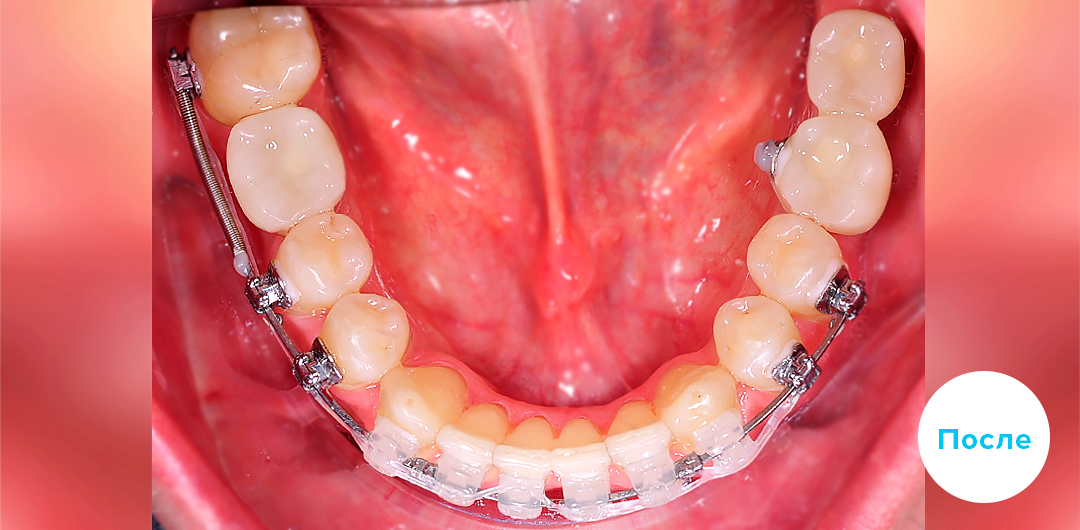

После

Ортодонтическое лечение подростка металлическими брекетами на 1 челюсти и аппаратом Гербста

Смотреть кейс